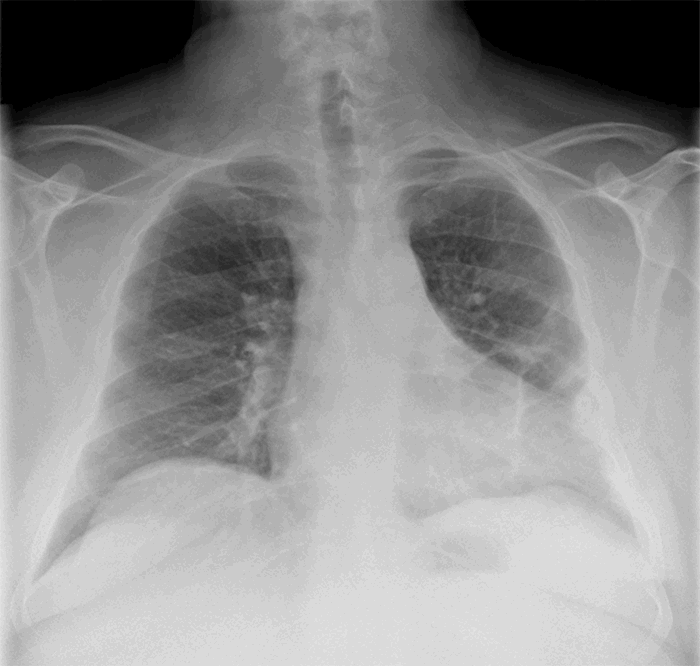

Two days after the initial presentation, the patient developed worsening dyspnea and pain in the left chest. He re-presented to the outside hospital where a computed tomography (CT) scan identified closed, minimally displaced left-sided rib fractures four through seven and a large extrapleural hematoma without evidence of active extravasation (Figure 2). The trachea and mediastinum significantly deviated to the right. The patient was then transferred to our level I trauma center for further management.

Figure 2. A) CT scan of the chest (coronal view) from outside hospital at re-presentation noting a large extrapleural hematoma and a rightward shift of the mediastinal structures. B) CT scan of the chest (axial view)